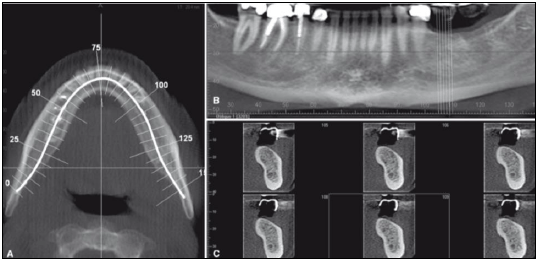

Observe a imagem a seguir.

Considerando que a imagem evidencia partes do mesmo exame, pode-se afirmar que se trata de uma: